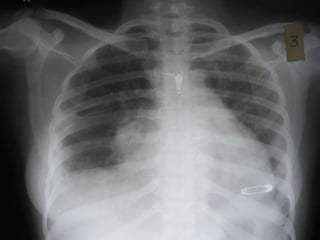

   Steroid dose hiked

   Fever disappears

   Cough subsides

   Chest pain subsides

   Chest X-Ray repeated after 1 week